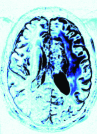

To examine the performance of our approach with brain MRI data when the assumptions of similarity between consecutive scans is not valid, we used retrospectively acquired data of a patient with GBM. The patient was scanned twice within an interval of five months, and exhibited changes between scans that occupy more than 50% of the brain region. We used T2-weighted FSE sequence (matrix: res = , 36 slices with thickness and no gap, TR/TE=, echo-train length=, flip angle=). We registered the follow-up scan to the baseline scan and examined the results of LACS-MRI (), CS-MRI and TCS-MRI with acceleration factors of 4, 6.4, and 10.6.

Table 3 shows the SNR values for different reconstructions and Figure 6 shows reconstruction results visually, at acceleration factor of 4 (25% of the k-space). In this case, there are major changes between the baseline and the follow-up scans due to therapy response. As a result, TCS-MRI exhibits poor performance in the vicinity of the changing tumor, since it is partially based on similarity between the consecutive scans, an assumption which is not valid in this case.

LACS-MRI, however, convergences to a result which is similar to CS-MRI. This is obtained thanks to the adaptive sampling and the weighting mechanism embedded in LACS-MRI, which reduces the weight given to the similarity to prior scan in the reconstruction process, if such a similarity does not exist.

Nyquist sampling (baseline)

Nyquist sampling (follow-up)

CS-MRI (follow-up)

TCS-MRI (follow-up)

LACS-MRI (follow-up)

Reconstruction result

Difference image

Reconstruction (zoom)